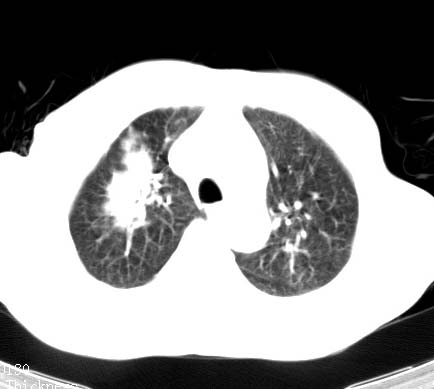

标题: CT14027:男性病人 71岁 咳嗽咳痰数周. [打印本页]

标题: CT14027:男性病人 71岁 咳嗽咳痰数周.

男性病人 71岁 咳嗽咳痰数周.诊断结核应该有保障吧!

结核是要考虑,但肺癌也不能排除.

右上肺结核,请结合痰检除外活动期;右上叶支气管官腔狭窄建议支气管镜或抗僗后随诊除外堵塞性改变。

高度怀疑肺癌,强烈要求纤支镜检查。

支持双上肺继发性肺结核。